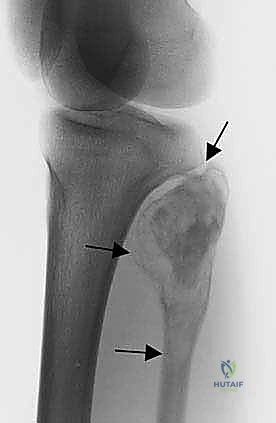

- الأشعة السينية (X-rays): الخطوة الأولى. تظهر التغيرات في الهيكل العظمي، تآكل العظم، أو التفاعلات السمحاقية (Periosteal reaction) التي تدل على وجود ورم.

* الساركوما العظمية (Osteosarcoma): الورم الخبيث الأكثر شيوعاً في العظام، وغالباً ما يصيب الأطفال والشباب. يتميز بنمو سريع وتدمير للعظم.

* ساركوما إيوينغ (Ewing Sarcoma): يصيب عادة الأطفال والمراهقين، وينشأ في تجويف النخاع العظمي للشظية.

* الساركوما الغضروفية (Chondrosarcoma): ينشأ من الخلايا الغضروفية، ويصيب عادة البالغين وكبار السن.